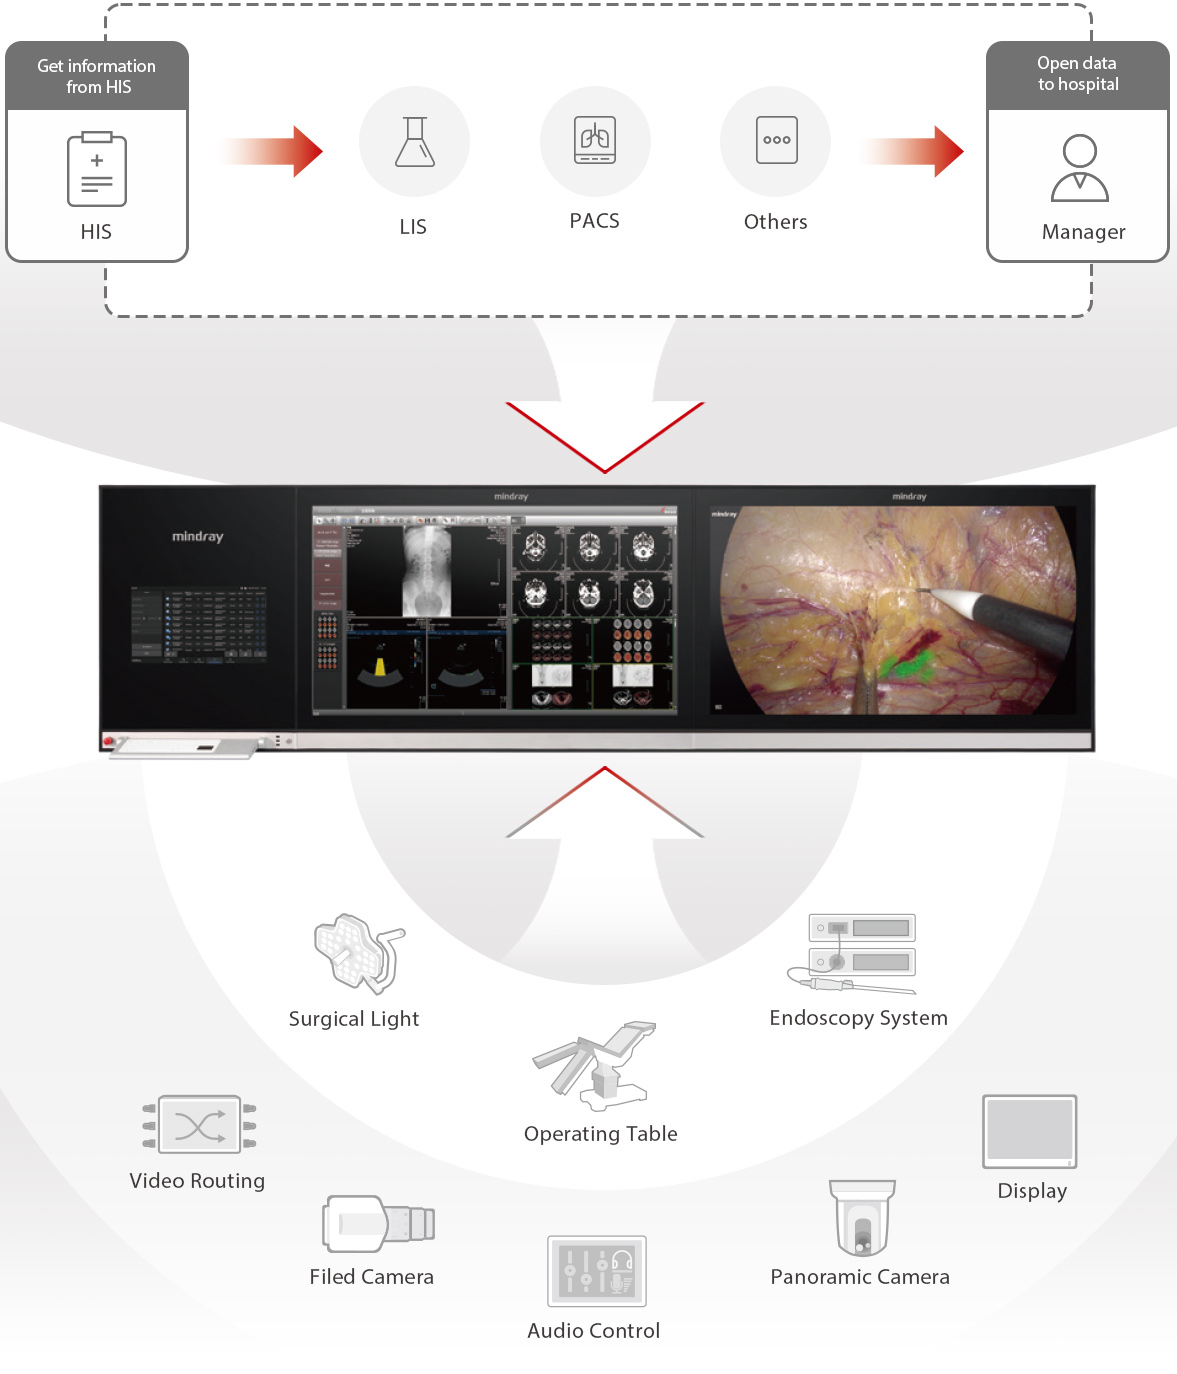

Admite una expansi├│n futura de quir├│fanos digitales dentro del hospital. Todas las salas est├Īn perfectamente interconectadas, lo que garantiza un flujo ininterrumpido de informaci├│n sin obst├Īculos.

En los quir├│fanos tradicionales, la diversidad de marcas de equipos, los m├®todos de control fragmentados y los sistemas de informaci├│n aislados dificultan considerablemente la eficiencia quir├║rgica y la seguridad de los pacientes. El sistema de quir├│fano digital de Mindray est├Ī dise?ado espec├Łficamente para abordar estos retos cr├Łticos.

Iluminaci├│n quir├║rgica

Mesa quir├║rgica

Sistema de endoscop├Ła

Enrutamiento de video

C├Īmara de campo

Control de audio

C├Īmara panor├Īmica

Pantalla

Capacidad de ampliar a futuro para contar con quir├│fanos totalmente conectados

La soluci├│n permite a?adir quir├│fanos digitales por fases, y estos se interconectan para tener flujo homog├®neo de la informaci├│n.

Sistema de control centralizado para los equipos del quir├│fano

Mindray proporciona una plataforma inteligente para el control de equipos quir├║rgicos. El sistema digital permite que el personal m├®dico controle la m├║sica de fondo, la iluminaci├│n, los sistemas de c├Īmara, las pantallas y m├Īs de forma eficiente. Adem├Īs, minimiza el movimiento frecuente entre las ├Īreas contaminadas y est├®riles durante la cirug├Ła, lo que reduce el riesgo de infecciones.